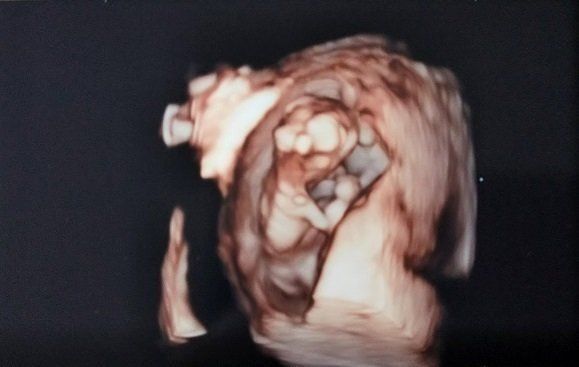

"おなかの中はどうなっていくの? エコー写真で振り返る、高齢ママのはじめての妊娠生活" -

あきらめかけたときに、うれしい妊娠!高齢でありがたく授かったわが子の記録 -